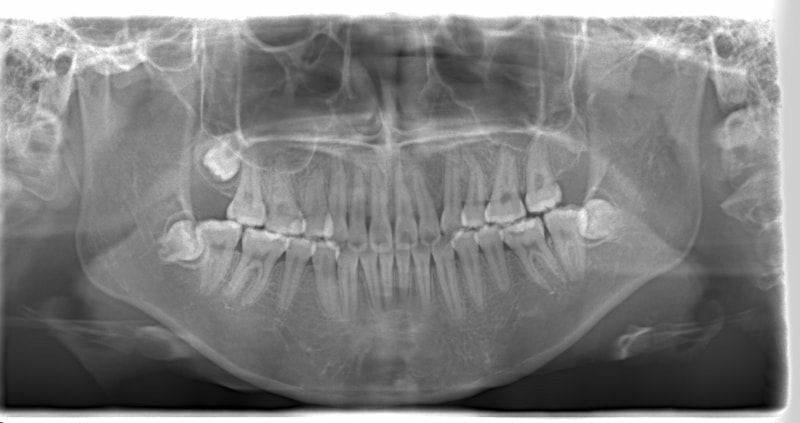

左上3番埋伏歯

治療法:フルパッシブブラケット:T21

治療前